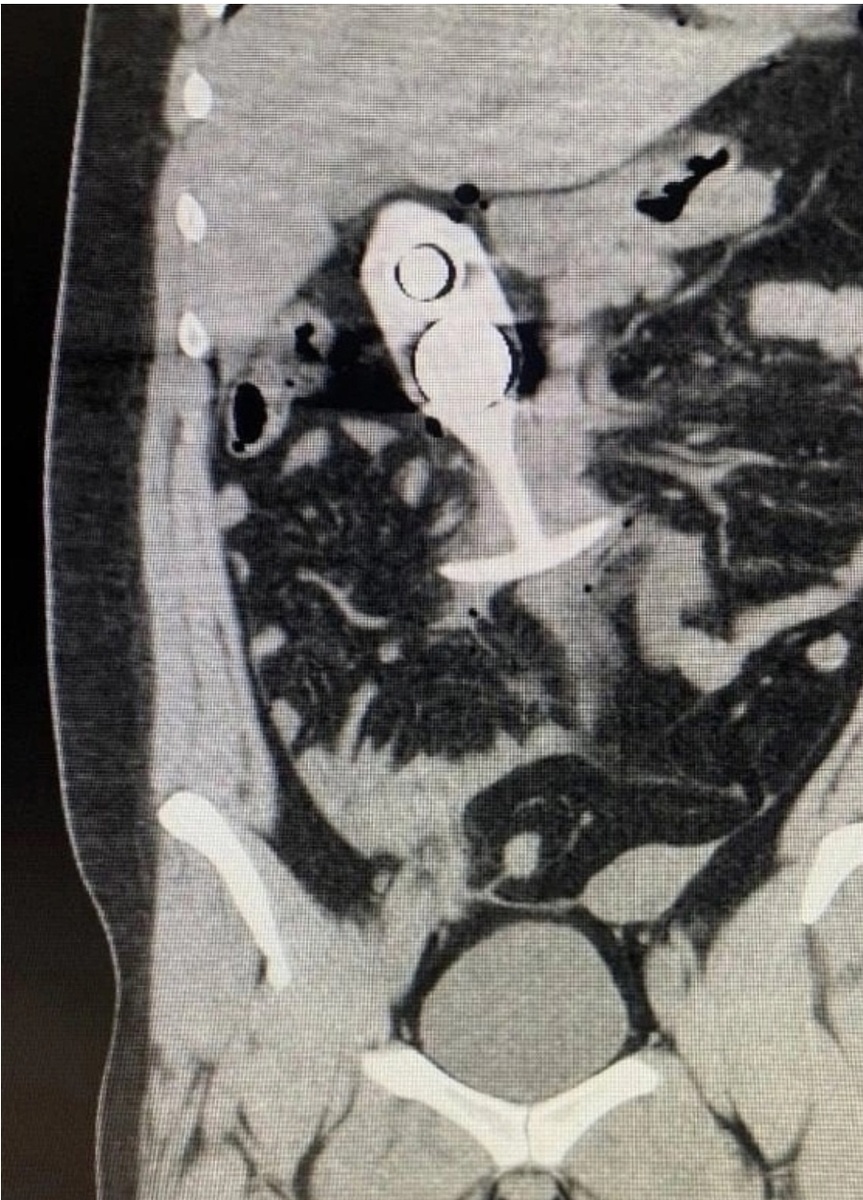

Скрины МРТ, на которых, мы уверены, отныне учат новых рентгенологов: «Вот, дети, смотрите — классический пример „синдрома магнитной пробки“».